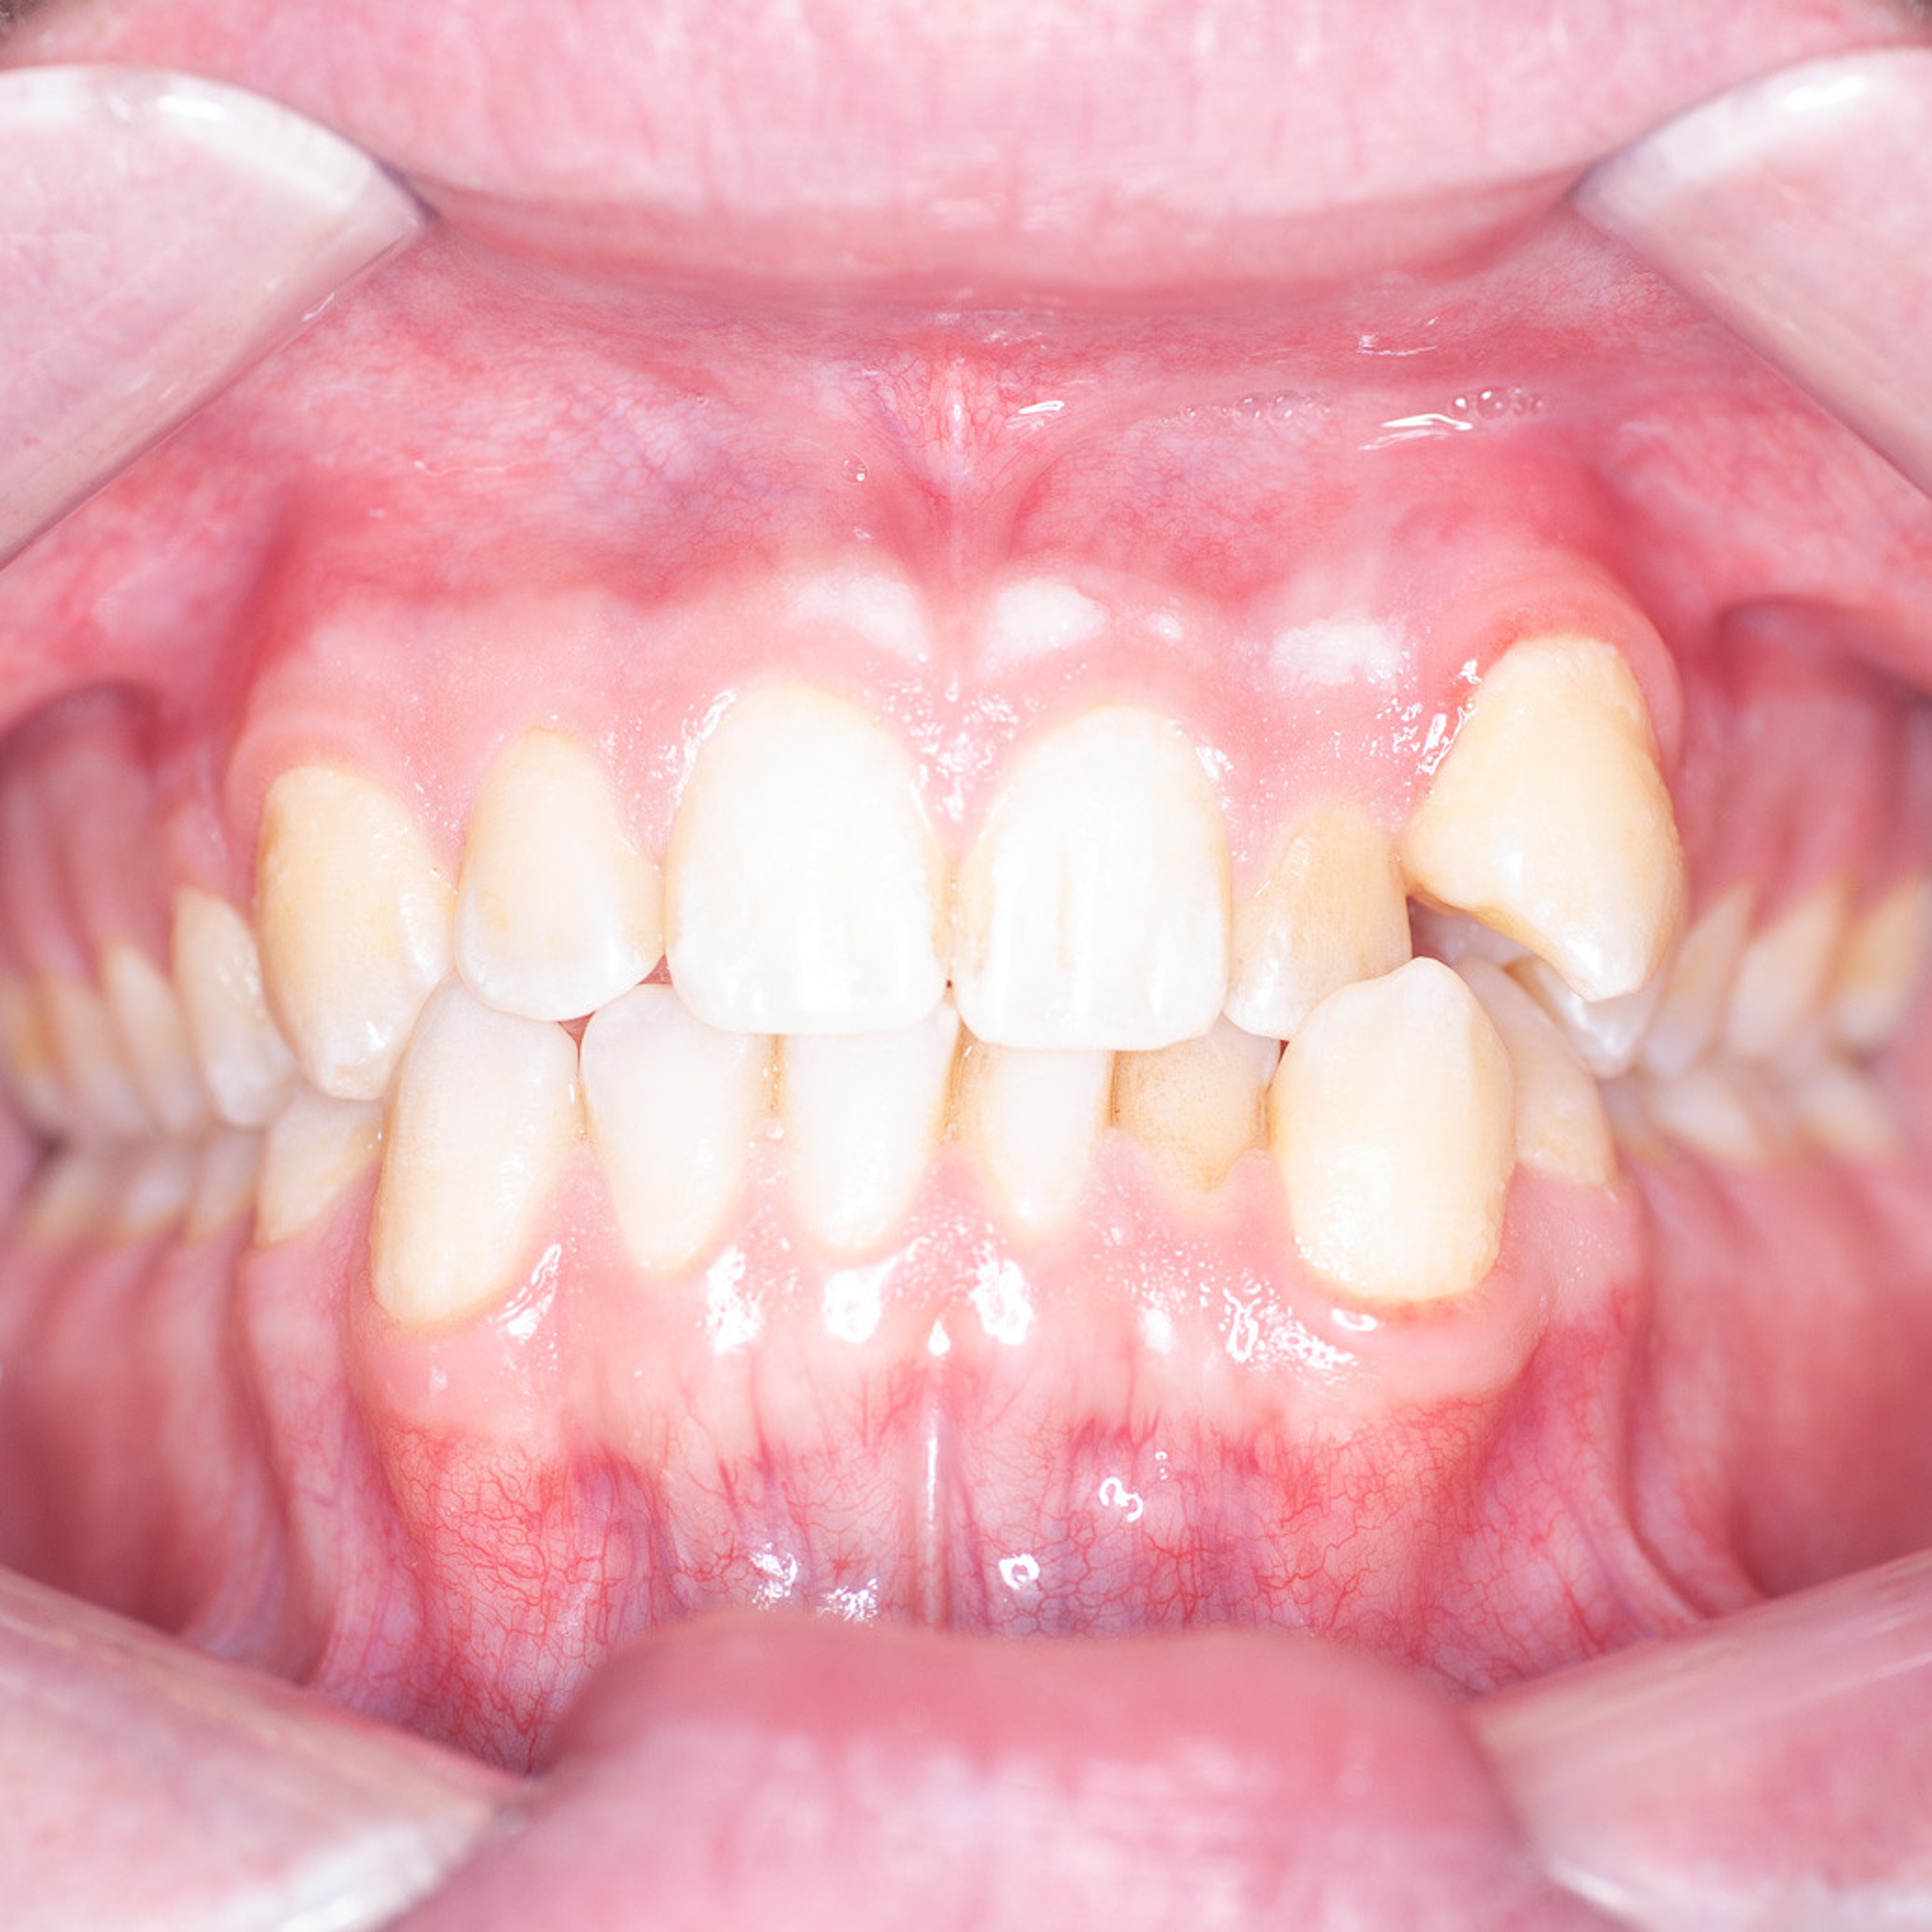

Фотографии учеников до обучения

Фотографии после обучения